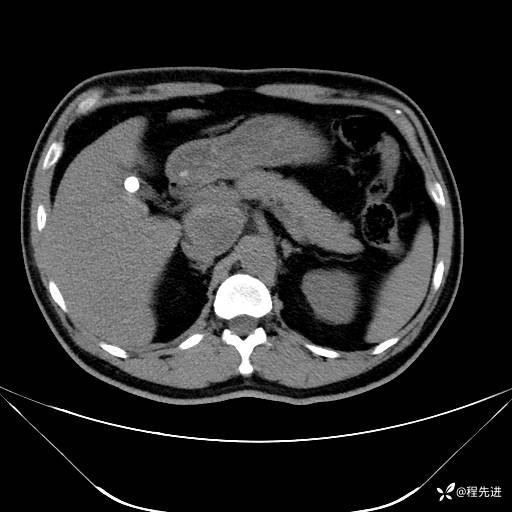

【腹盆】特别精彩病例|发现腹膜后肿物1月余

患者性别:男

患者年龄:42岁

主诉:发现腹膜后肿物1月余

现病史:患者1月余前查体,行超声检查提示:后腹膜囊实性肿块;慢性胆囊炎伴胆囊内结石;无腹痛腹胀,不伴腹泻发热等;偶感腰背部酸痛。

CT平扫+增强: